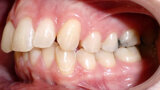

ClearCorrect treatment of crowding